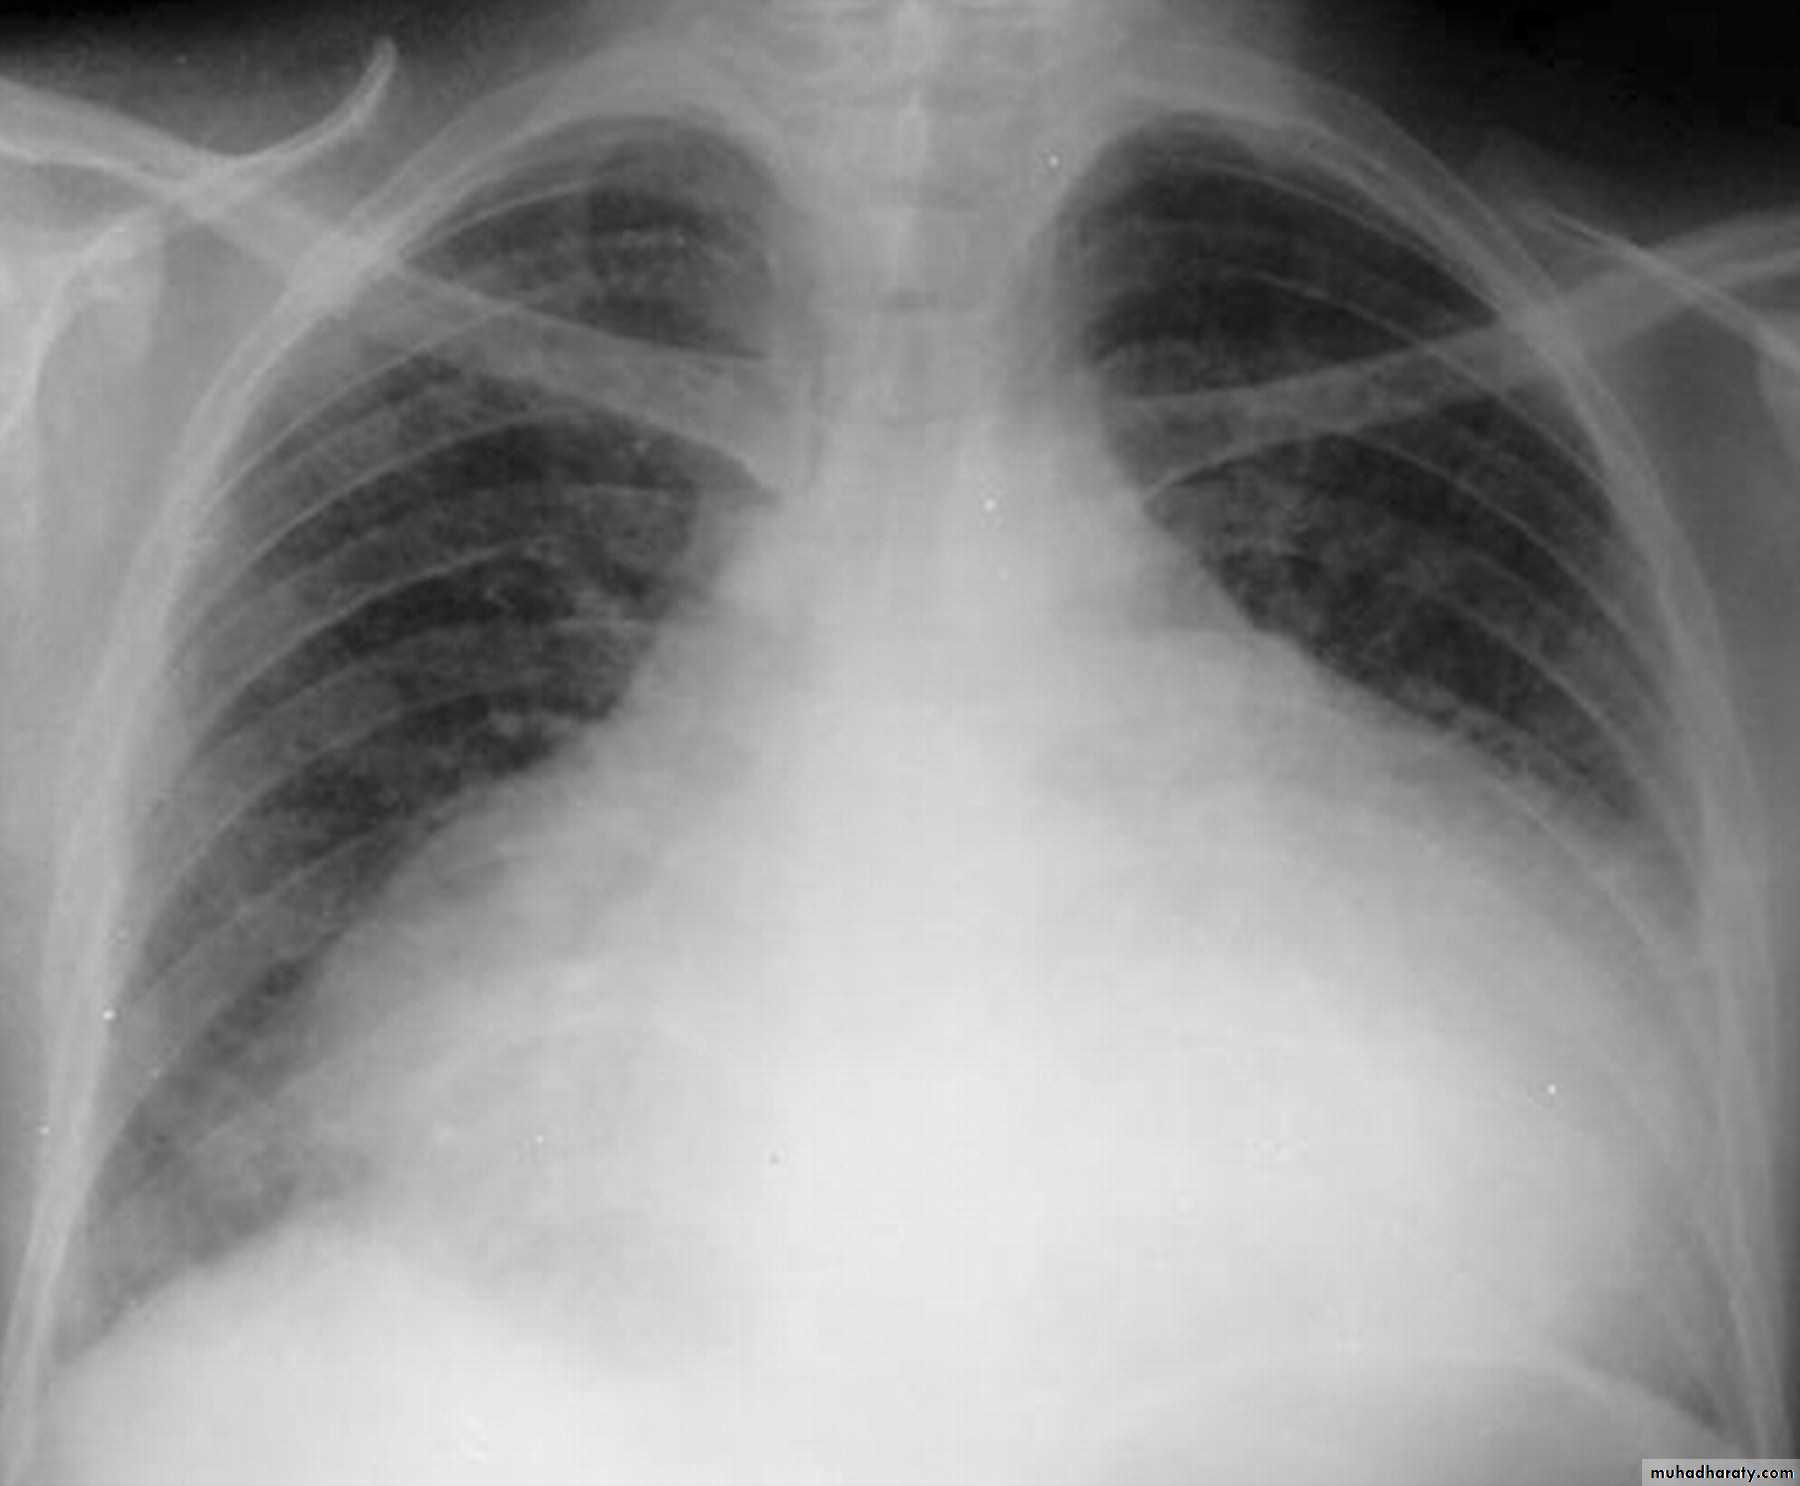

Homogenus opacity of the left hemithorax with shifting of the trachea to the same sidePleural effusion

Homogenus opacity of right lower zone with meniscus signOblitration of right cardiophrenic and costophrenic angles

Homogenus opacity of the right hemithorax

Oblitration of cardiophrenic and costophrenic angles

Shifting of the trachea to the opposite side

Pleural effusion

Homogenus opacity of right lower lobe with Oblitration of right cardiophrenic and costophrenic angles.

Meniscus sign